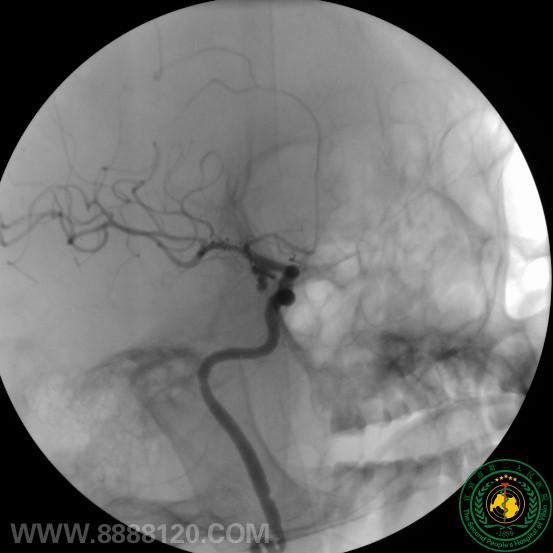

我科采用Lvis支架半释放技术完成复杂后交通动脉瘤介入治疗

我科采用Lvis支架半释放技术完成复杂后交通动脉瘤介入治疗9675